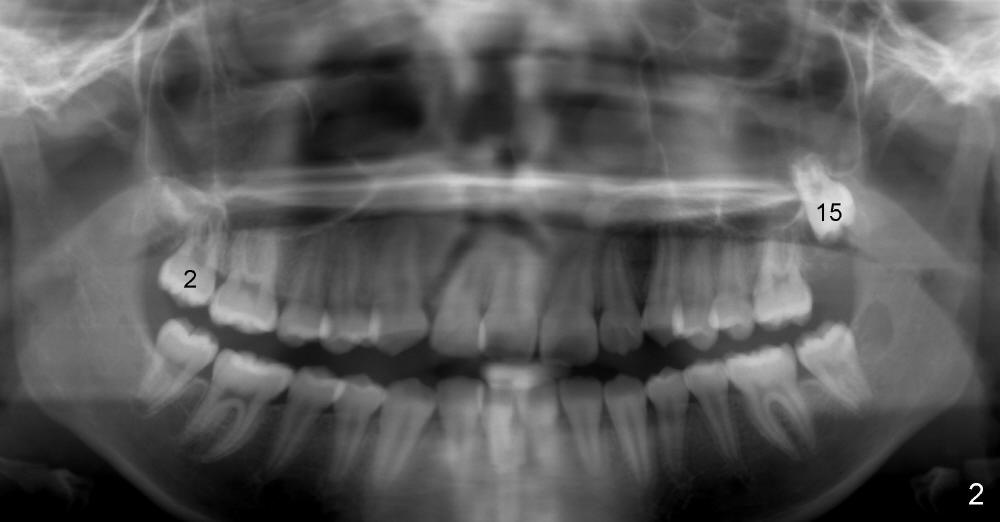

When Willie was 11 years 2 months old, the upper 2nd molars are unerupted (Fig.1: #2,15).

Now at the age of 12 years 10 months, #2 has erupted whereas #15 remains unerupted (Fig.2).